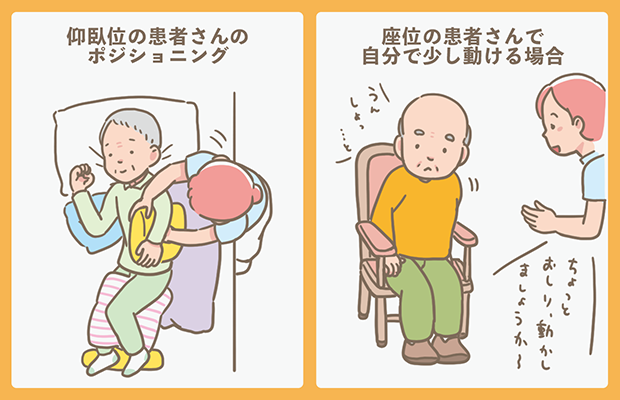

実践します!褥瘡ケア「いつもの方法を見直してみよう」エール在宅診療所。

褥瘡の予防と観察ポイント見て!わかる!病態生理と看護 花子のまとめノート。